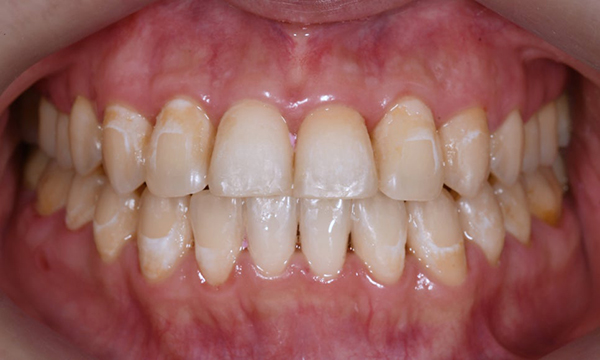

본 20대 여자 환자분은 약 한 달전 교정 치료를 끝마친 후에 앞니에 화이트 스팟이 생겼다는 이유로 감사하게도 경기도에서 저희 치과까지 찾아와주셨습니다. 일반적으로 교정 치료 후 생긴 반점치는 장치 형태 주변으로 생기는데, 본 환자의 경우 앞니 2개에 심하지는 않지만 중앙 부분에 화이트 스팟이 생겼습니다.